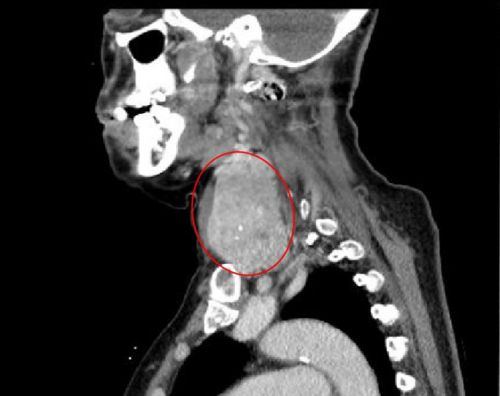

ct显示:左侧甲状腺肿瘤有成人拳头大小。